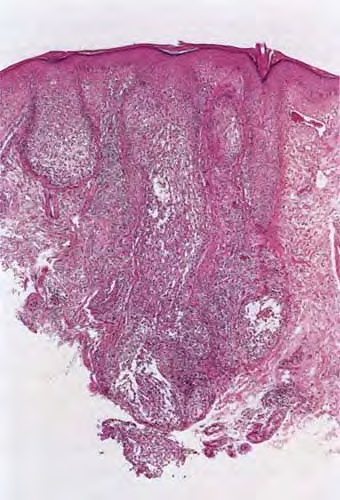

In 1957, Pinkus described alopecia mucinosa, the term used when follicular mucinosis affects terminal hairbearing areas and is associated with hair loss . Papules and plaques may be present or inconspicuous in this form, which may show only alopecia. Scarring is seen more commonly when alopecia mucinosa is associated with cutaneous T-cell lymphoma. Others claim that alopecia mucinosa is simply one of the many morphologic variants of mycosis fungoides , whereas LeBoit and LeBoit acknowledged the paradoxes of alopecia mucinosa that have led to the debate over classification (. Histopathology. Within the outer root sheath and sebaceous gland epithelium, there is reticular epithelial degeneration that sometimes evolves into more extensive cavitation within which mucin is deposited . Occasionally, little mucin can be detected, perhaps because of removal of this water-soluble material in the processing procedure. The deposited mucin is an acid mucopolysaccharide that stains metachromatically with toluidine blue at pH 3.0, as well as with Alcian blue at acid pH. The fact that it can be substantially removed by digestion with hyaluronidase demonstrates that the mucin is predominantly hyaluronic acid. Colloidal iron stain may also be used for its detection. |

Inflammation is composed of lymphocytes and histiocytes, but there can also be eosinophils. There may be exocytosis into the outer root sheath epithelium of the infundibulum and the sebaceous gland epithelium. Although individual pathologic criteria are not absolutely diagnostic of the type of |

follicular mucinosis (primary or secondary), features that have been proposed as favoring a lymphoma-associated lesion include an atypical lymphocytic infiltrate or increased density of the perifollicular infiltrate with substantial folliculotropism . This study also suggested that a prominent eosinophilic infiltrate and more substantial mucin deposition tend to favor a benign process, but a subsequent study failed to substantiate these findings . |